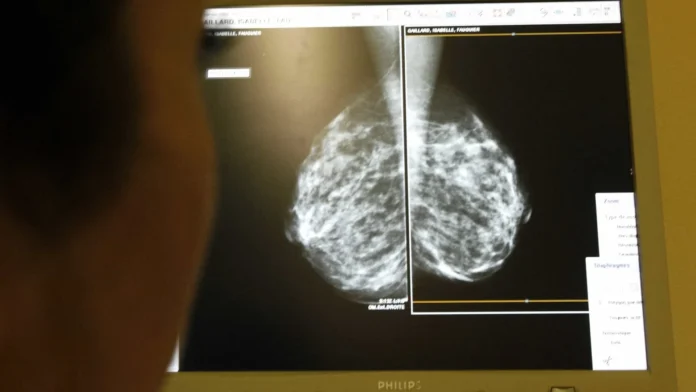

Fora do sistema digestório, o câncer de pulmão e de órgãos do sistema respiratório é o mais letal, com 22.853 mortes registradas ao longo do ano. Já os tipos mais incidentes variam conforme o gênero: o câncer de mama é o mais comum entre as mulheres, enquanto o de próstata lidera entre os homens.